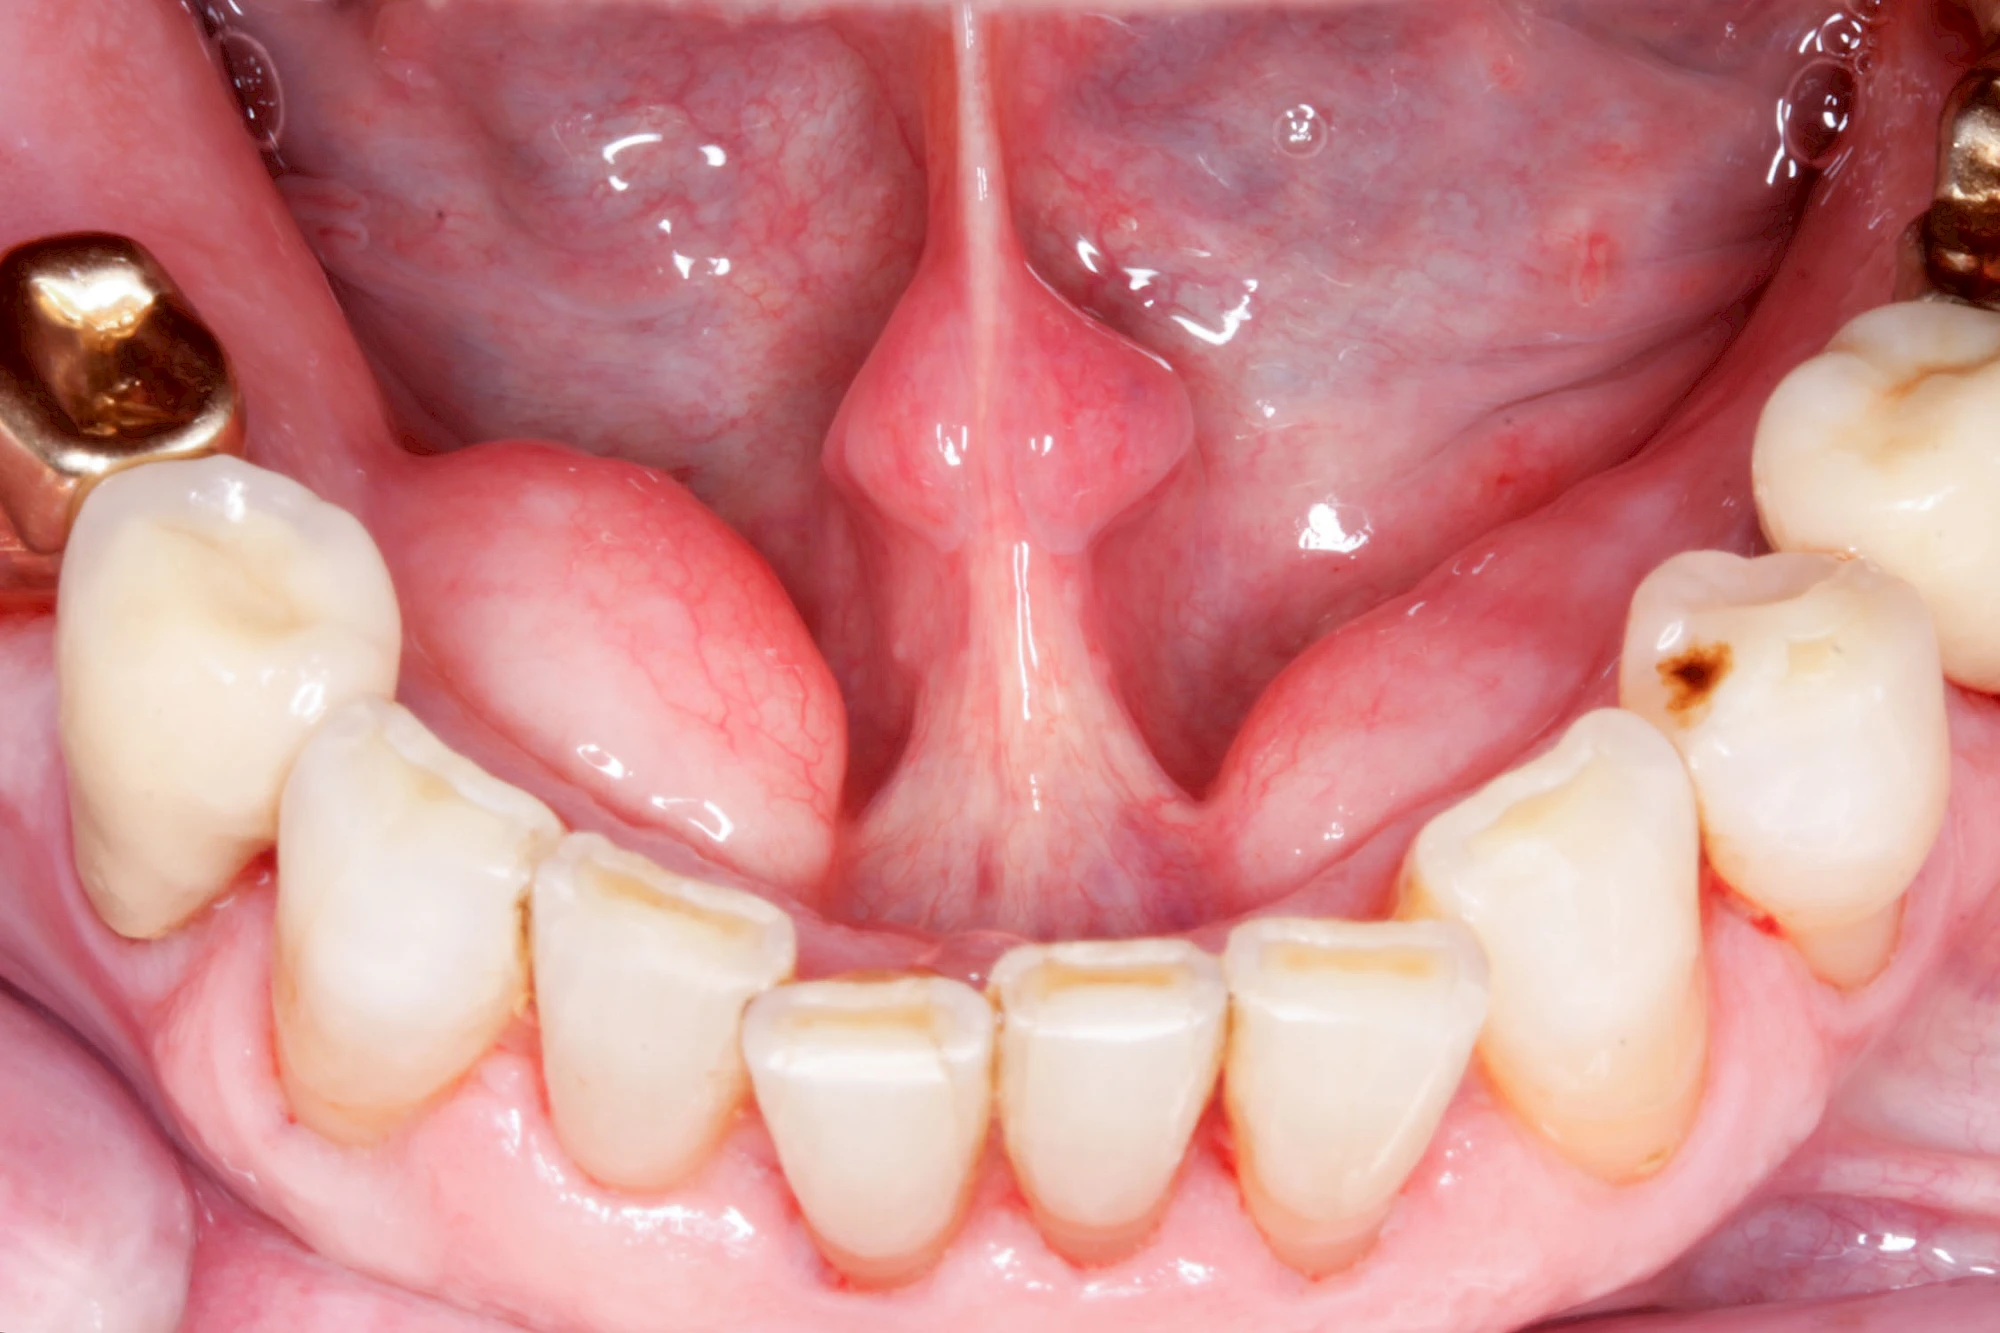

Lippen-Kiefer-Gaumenspalte

Lippen-Kiefer-Gaumenspalten (LKG-Spalte) sind angeborene Fehlbildungen im Mund-Kiefer-Gesichtsbereich. Die Gewebestrukturen im Bereich des Oberkiefers sind im Zuge der Entwicklungen bis zur Geburt nicht zusammengewachsen. Diese Fehlbildung zählt zu den häufigsten Fehlbildungen des Menschen, von 500 Neugeborenen ist eines betroffen. Die Fehlbildungen können sich auf Lippe, Gaumen und Kiefer allein beschränken, treten häufig aber kombiniert und in seltenen Fällen sogar beidseits auf.

Heute werden in Deutschland Menschen mit Lippen-Kiefer-Gaumenspalten bereits ab Geburt von Experten verschiedener Fachrichtungen (Mund-Kiefer-Gesichtschirurgen, Kieferorthopäden, Logopäden) betreut, damit entsprechende Korrekturen schon frühzeitig erfolgen können. Gerade jedoch bei älteren Menschen ist dies nicht immer geschehen. Diese Menschen tragen häufig technisch aufwendige Zahnprothesen.